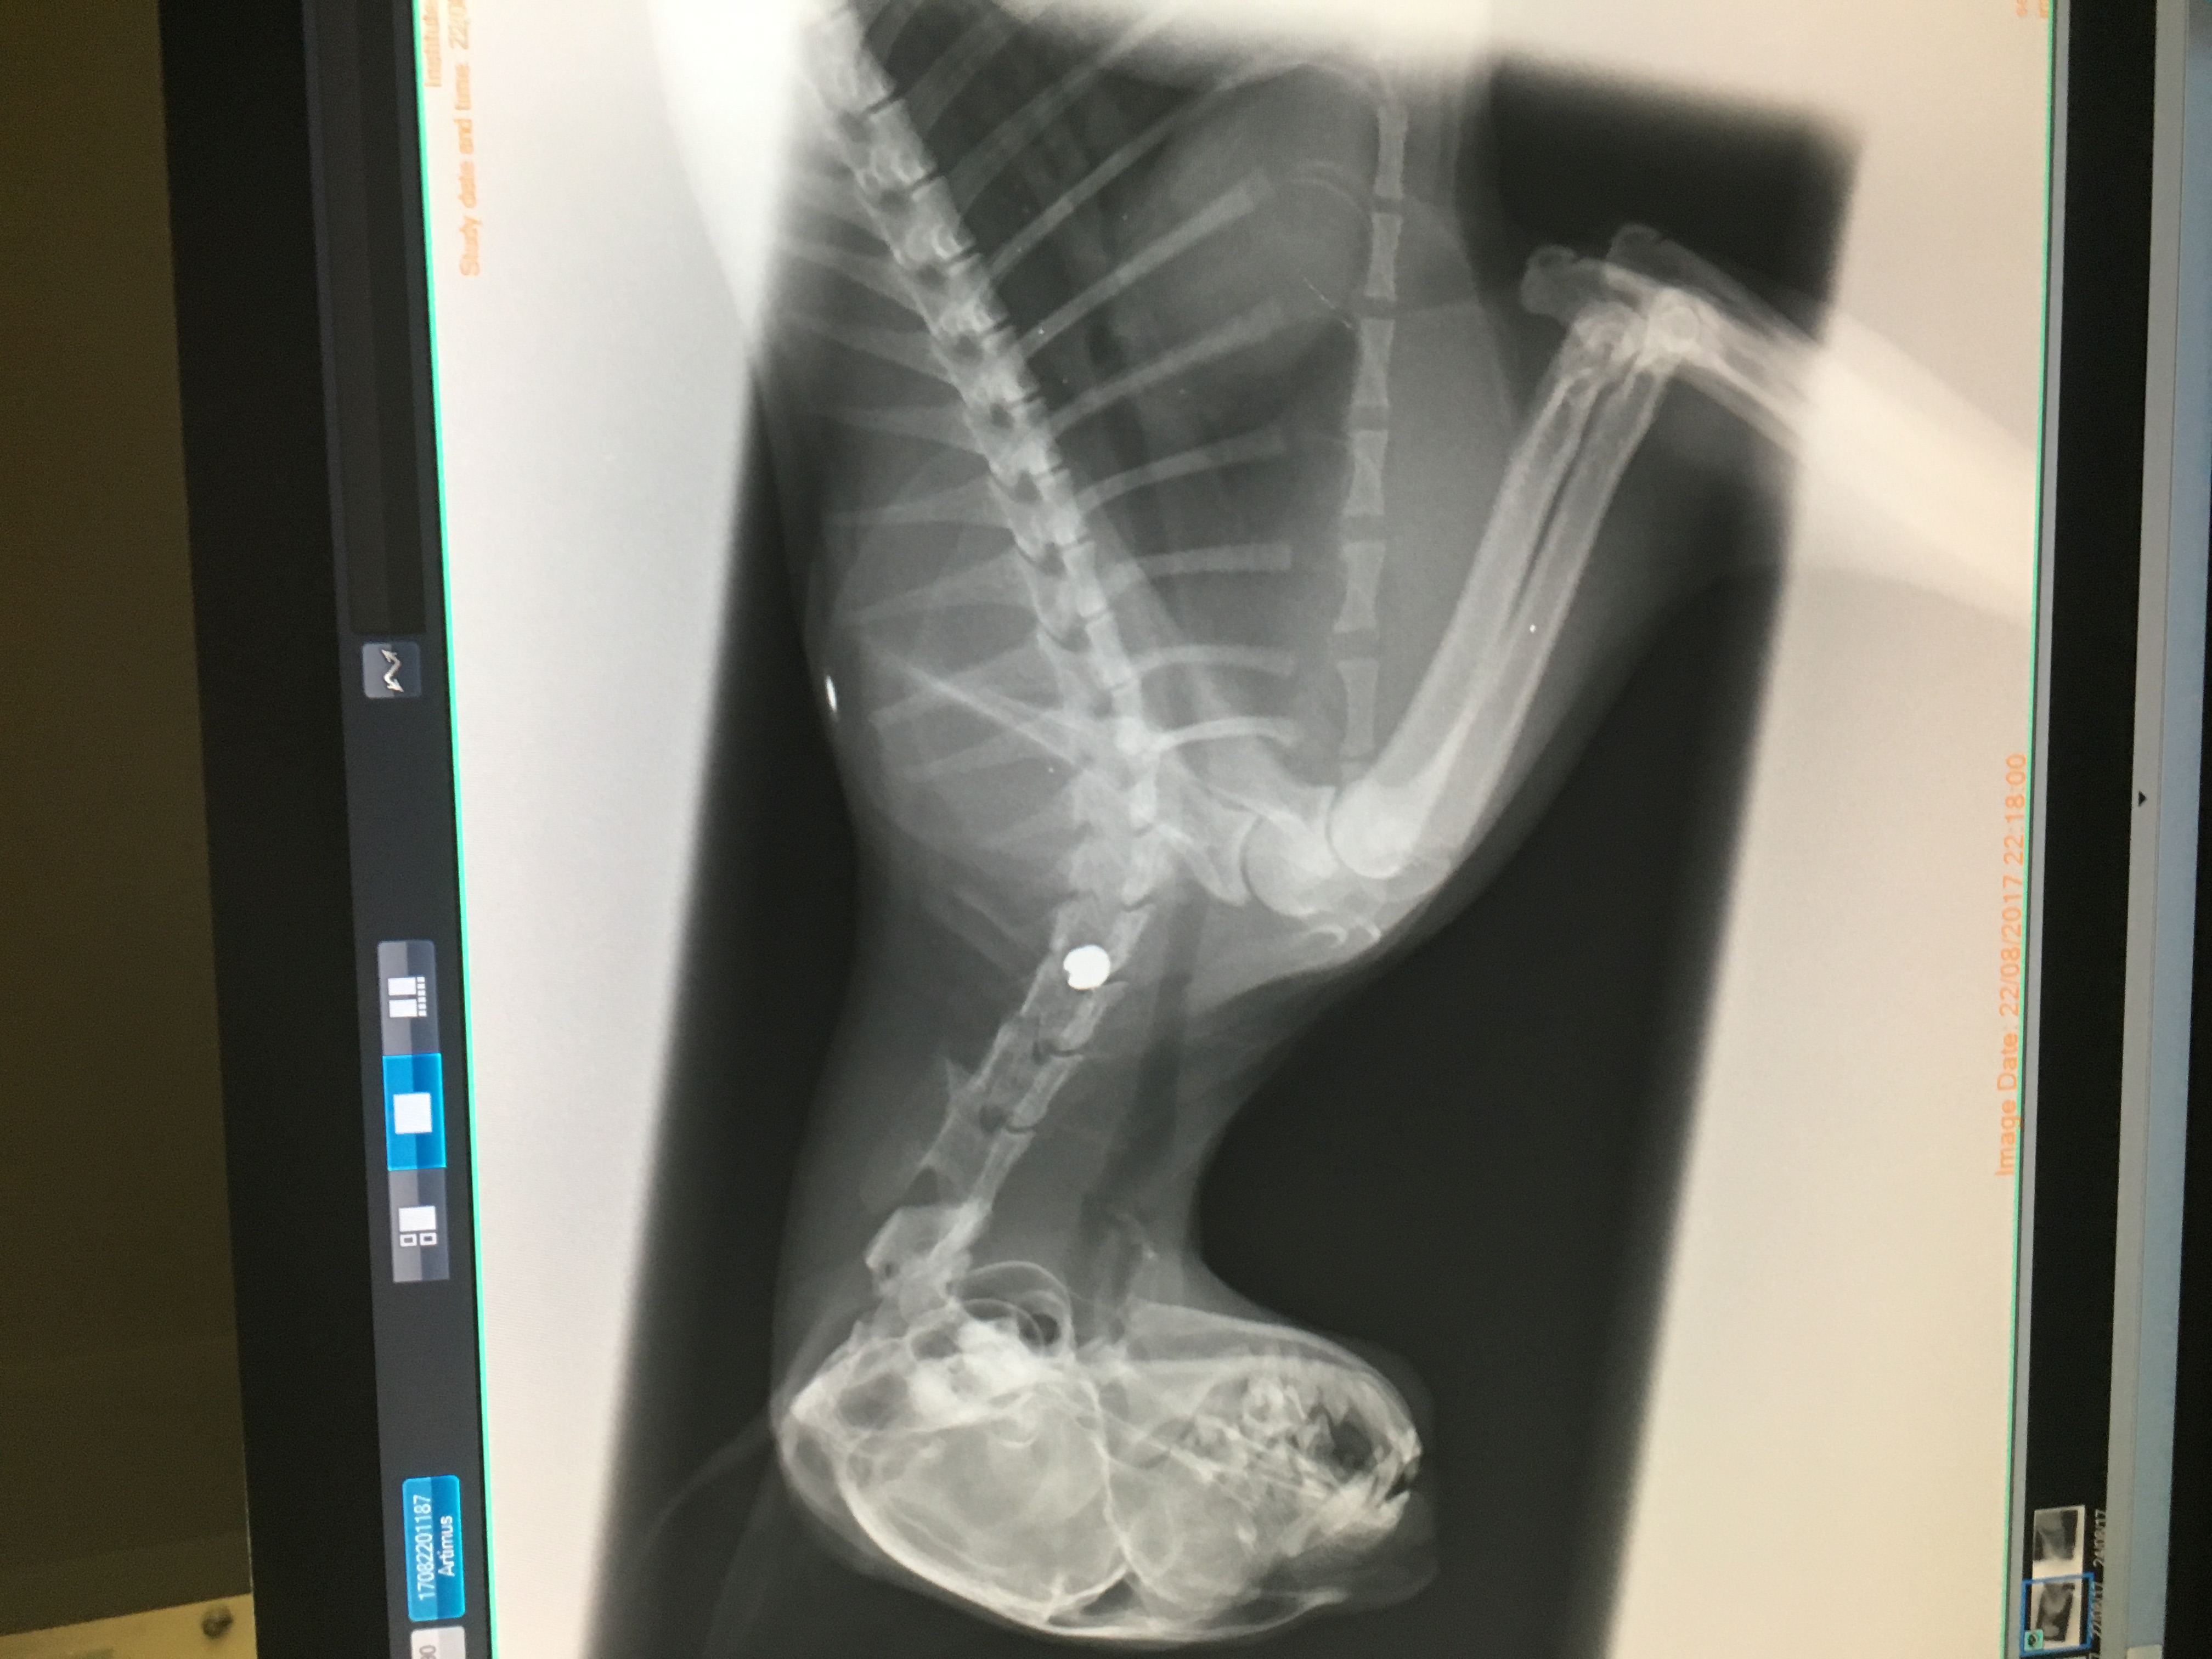

This is my kitten Artie. On Monday 21st August he was shot in the neck with an air rifle. The pellet has hit Artie's spinal cord. This has paralised his whole right side of his body. With surgery the pellet can be removed and he can begin his recovery, allowing him to eventually walk again. Unfortunately his insurance and the little money me and my fiance had towards our wedding fund has only covered the inital costs for the x-rays and CT scan. We now need more money to cover the surgery costs. Artie is our baby and a massive part of our lives (he even helped me with the proposal). It is his first birthday on 3rd September. It would mean so much if anyone could help us bring our fur baby home.

Just a bit of an update for everyone. Artie has had his surgery, when they took the pellet out they found that it had punctured his wind pipe. Fortunately they have successfully removed it now and stitched him up. He's having trouble breathing at the moment. However he is able to move all of his limbs a bit now which is good. The vets think he will make a full recovery providing there are no further complications. He is staying at the vets for another 2 weeks minimum to heal. Thanks for everyone's support. From Cyrus and Georgia Mason